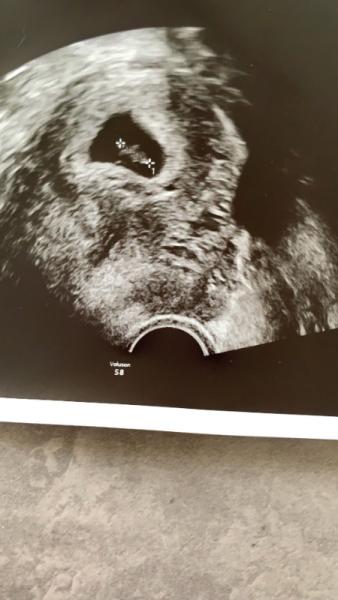

Erstmal wurden die HCG Werte besprochen und sie meinte gleich, dass es nicht gut aussieht und der Wert von Montag Nachmittag auf Dienstag sogar etwas gesunken ist. Sie fragte, ob ich eine Blutung hatte, was ich zum Glück verneinen konnte. Dann doch noch ne Untersuchung um zu schauen, ob die Fruchthöhle überhaupt noch zu sehen ist. Meine Laune war im Keller und ich musste erstmal schlucken um diese Nachricht zu verdauen Dann der Ultraschall: in der Fruchthöhle ganz eindeutige ein Embryo zu sehen und auch die Herzaktionen Ich habe vor lauter Freude geweint und wusste gar nicht, wie mir geschieht. Nach der Abmessung bin ich genau richtig bei 7+4, so wie es auch sein sollte. Ich bin total happy und muss das erstmal für mich verdauen. Letztes Mal hat sich das kleine wohl dann gut versteckt.

Bild zu Zurück vom FA, was für ein auf und ab 🙈 - Forum für April - Mamis